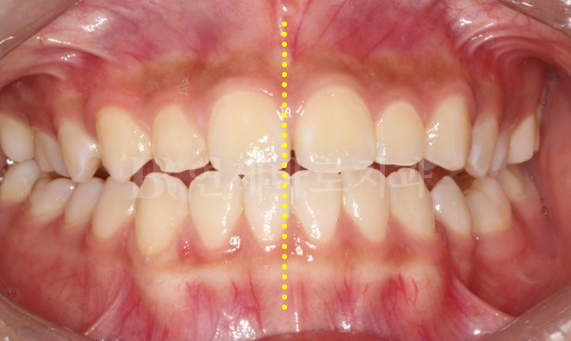

비대칭 교정 CASE

-

비대칭 교정

얼굴 중심선을 기준으로 좌우 균형이 어긋나 있거나 대칭이 되지 않는 경우를 말합니다. 일반적으로 치아 또는 얼굴 형태와 같이 삐뚤어져 있는 경우가 많으며, 주걱턱, 무턱 증상과 동반되어 나타나는 경우가 많습니다.